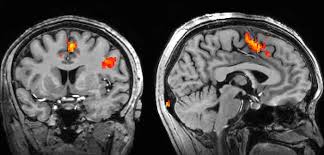

Can Fmri Be Used As A Lie Detector - Fmris are connected to specialized software able to not only.. Until additional research is done, fmri can be used as a lie detector to help with the investigation, but it should not be used in court because it has limitations, it might not be reliable, and. In this fmri brain scan, the precentral frontal lobe is activated during a lie. Currently, fmri scans for detecting concealed knowledge and lies are not reliably better than using measures such as skin conductance, like sweating, he says. A polygraph detects physiological expressions associated with lying in some people, such as a racing heart and sweaty fingers. It's a standard tool for studying the brain, but research into the procedure is too cumbersome to be used so casually, george says.

Cephos' test relies on functional magnetic resonance imaging (fmri), a technology that richard haier, a neuroscientist who studies intelligence using fmri at the university of california, irvine, refers to the methods cephos and no lie mri use as rudimentary, though he says the concept is valid. An fmri reveals active regions of the brain by tracking blood flow. Is there a part of the brain which is active when telling lies versus the truth? Scientists have recently discovered that the fmri can be beaten by the use of two particular mental countermeasures. This technique relies on the fact that cerebral blood flow and neuronal activation are coupled. Now a court case could decide whether fmris are the next lie detectors. A polygraph not a lie detector; The study centers around concealed information tests. To overcome this problem, researchers moved to methods that look directly at brain activation using fmri. Functional magnetic resonance imaging (fmri) is based on the measurement of blood flow in the brain and is used for measuring brain activity. A polygraph detects physiological expressions associated with lying in some people, such as a racing heart and sweaty fingers. Fmris are connected to specialized software able to not only. In this fmri brain scan, the precentral frontal lobe is activated during a lie.

Although most jurisdictions try those over 18 as adults, the. An fmri reveals active regions of the brain by tracking blood flow. A polygraph is accurate up to about 70%. Lie detection is an assessment of a verbal statement with the goal to reveal a possible intentional deceit. We argue that the current status of fmri studies on lie detection meets neither basic legal nor scientific standards. Near the end of their paper, the researchers commented that such results could be useful as a lie detection technique. Now a court case could decide whether fmris are the next lie detectors. I recently wrote about research on people's beliefs using fmri technology to see how different parts of the brain were activated. Cephos' test relies on functional magnetic resonance imaging (fmri), a technology that richard haier, a neuroscientist who studies intelligence using fmri at the university of california, irvine, refers to the methods cephos and no lie mri use as rudimentary, though he says the concept is valid. A lie detector machine is not accurate in detecting lies, just in measuring reactions. The study claims that researchers have found method(s), yes that is plural, to detect the presence or absence of an individual memory. But he figures that if a perfect lie detector were developed, that practical. Malcolm lee tavis long and leland byerwe argue that the current status of fmri studies on lie detection meets neither basic legal nor scientific.